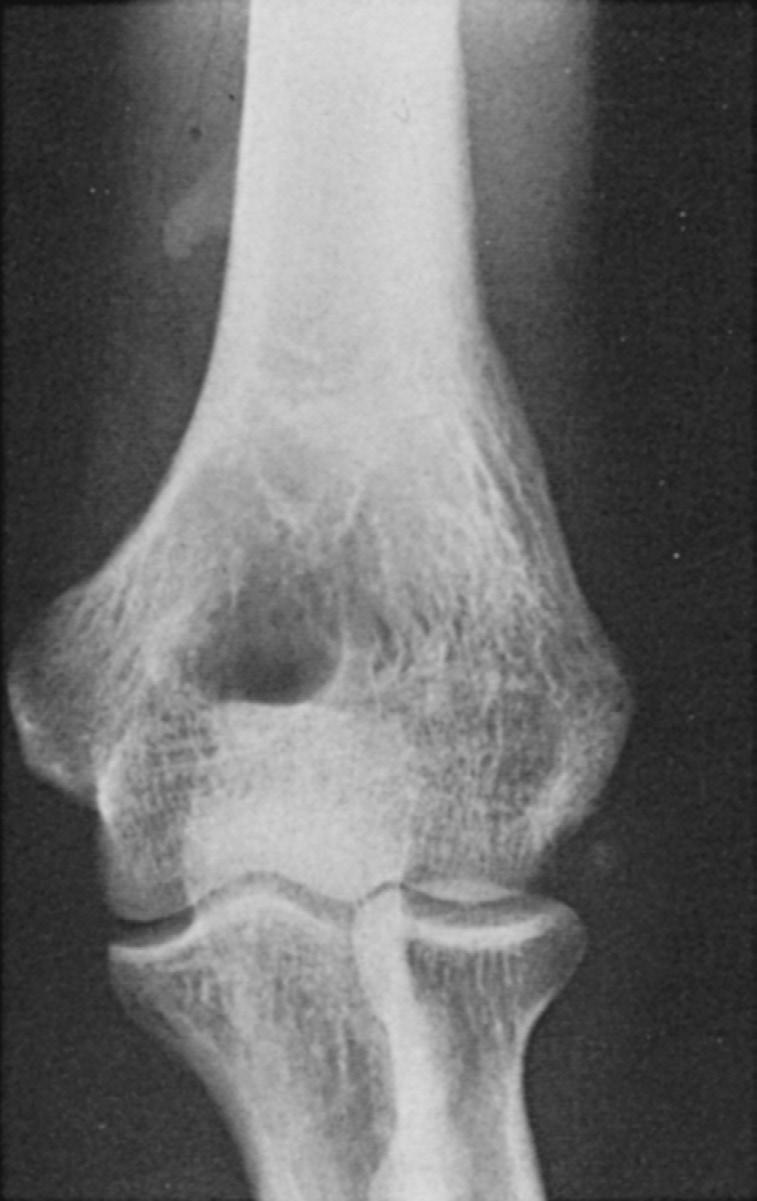

The distal humerus consists of an arch formed by two condyles that support the ar ticular elements of the trochlea and capitellum (Fig 2.5).

Medial to the trochlea, the prominent medial epicondyle serves as a source of attachment of the medial ulnar collateral ligament and the flexor-pronator group of muscles. Laterally, the lateral epicondyle is located just proximal to the capitellum and is much less prominent than the medial epicondyle. The lateral ulnar collateral ligament and the supinator-extensor muscle group originate from the flat, irregular surface of the lateral epicondyle.

Anteriorly, the radial and coronoid fossae accommodate the radial head and coronoid process during flexion. Posteriorly, the olecranon fossa receives the tip of the olecranon.

FIG 2.5 (A) The bony landmarks of the anterior aspect of the distal humerus. Note the 6-degree valgus angulation of the flexion axis and long axis of the humerus. (B) The prominent medial and lateral supracondylar bony columns as well as other landmarks of the posterior aspect of the distal humerus.